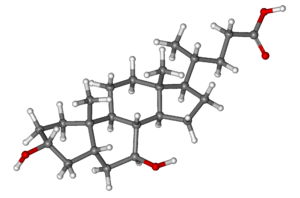

- In cholestatic liver disease, (where the flow of bile is affected due to cystic fibrosis[30]) a medication called ursodeoxycholic acid (URSO, also referred to as UDCA) may be given.[31]